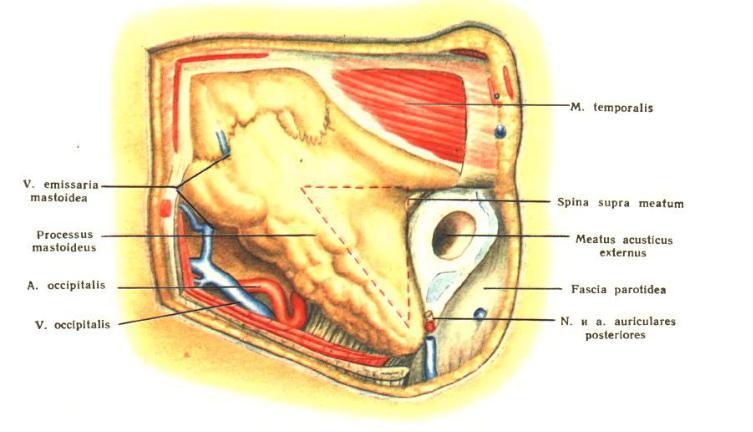

Анатомия сосцевидного отростка